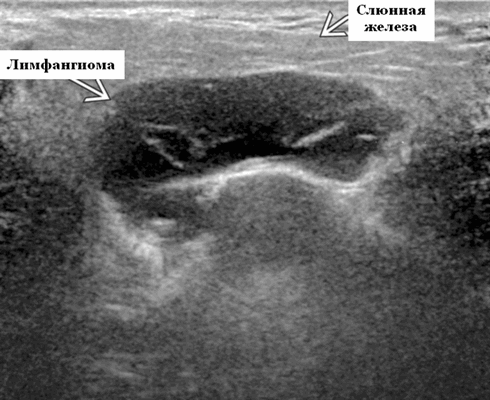

Ультразвуковая визуализация слюнной железы. Общие особенности

- Расположение. 75% возникают в области головы и шеи (наиболее часто). На подъязычной области шеи ЛМ чаще всего встречаются в заднем треугольнике, тогда как жевательные и поднижнечелюстные пространства - самые частые места надподъязычной зоны шеи. Интрапаротидное расположение встречается нечасто, при этом поражение может быть транспространственным, затрагивая несколько смежных пространств. 20% поражают опухолей подмышечную впадину. Реже поражается средостение, пах и забрюшинное пространство.

- Морфология. Однокамерное или, чаще, многокамерное поражение. Может содержать округлые или вкрапленные кистозные пространства. Имеет тенденцию проникать между нормальными структурами без какого-либо масс эффекта

Результаты ультразвукового исследования. Серошкальное УЗИ. Более крупные околоушные лимфангиомы могут быть обнаружены при пренатальном УЗИ. Чаще мультилокулярный, чем монокулярный. Кистозные пространства могут быть округлыми или вкраплениями. Поверхностные поражения сжимаются ультразвуковым датчиком. Внешний вид зависит от того, было ли ранее кровотечение / инфекция. Негеморрагический / неинфицированный лимфаангимоы выглядят на УЗИ как однокамерные или многокамерные (чаще) анэхогенные сжимаемые кисты с тонкими стенками и промежуточными септами. Несмотря на большие размеры, существенного масс эффекта нет. Тонкие незаметные стенки с задним акустическим усилением. Цветной допплер: в области поражения нет кровеносных сосудов. Геморрагический / инфицированный тип лимфатической мальформации. Однокамерные или многокамерные гетерогенные кисты с неровными стенками, внутренним дебрисом. Несжимаемые датчиком и гипоэхогенные полости с толстыми стенками и перегородками. Уровни жидкости-жидкости из-за осаждения и разделения жидкостей предполагают предшествующее кровотечение. Цветной допплер: при заражении; васкуляризация может быть видна в стенках, перегородках и прилегающих мягких тканях